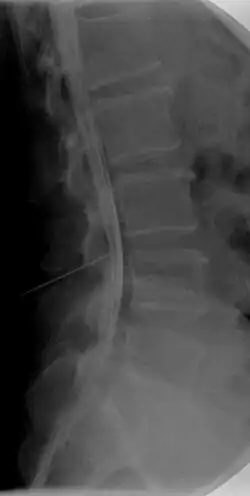

Caudografie is in de geneeskunde een onderzoeksmethode waarbij de cauda equina in beeld wordt gebracht door het onderste deel van het ruggenmergskanaal met contrastvloeistof te vullen door middel van een lumbale punctie en dan röntgenfoto's te nemen. Op deze manier kan meestal de oorzaak van een caudasyndroom in beeld gebracht worden.